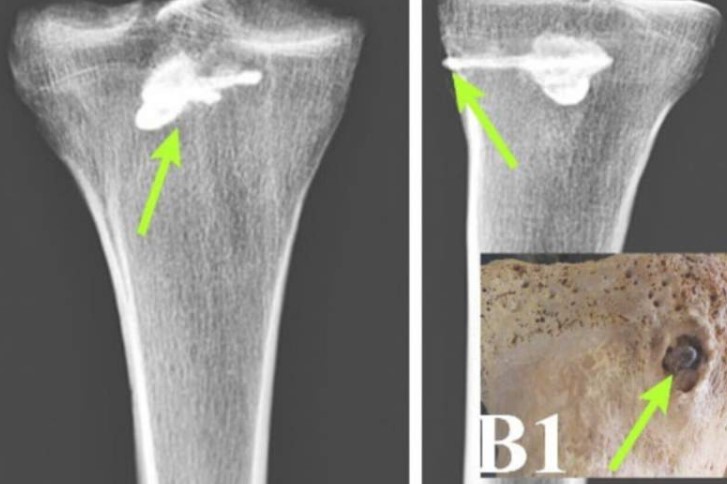

وكشفت الأشعة السينية الفلورية وتحليل المعادن الكمومي والتصوير المقطعي المحوسب لعظام الرجل عن وجود جسم معدني مغروس في ساقه اليمنى.

حددت أبحاث إضافية الجسم على أنه رأس سهم معدني ثلاثي الشفرات على الطراز البارثي يبلغ طوله حوالي بوصتين وعرضه حوالي نصف بوصة.

كشف تحليل عظمة قصبة الرجل عن بعض علامات التئام الجرح، مما يشير إلى أنه عاش لفترة بعد الاصطدام، يُبرز التصميم المعقد لرأس السهم، الذي يتميز بدقته، المهارة التكنولوجية والمعدنية البارثية، ومع ذلك، فإن عدم القدرة على إزالة رأس السهم المُطعّم، يُشير على الأقل إلى بعض أوجه القصور في ممارساتهم الجراحية، مما يُلقي الضوء على القيود الطبية في المنطقة.